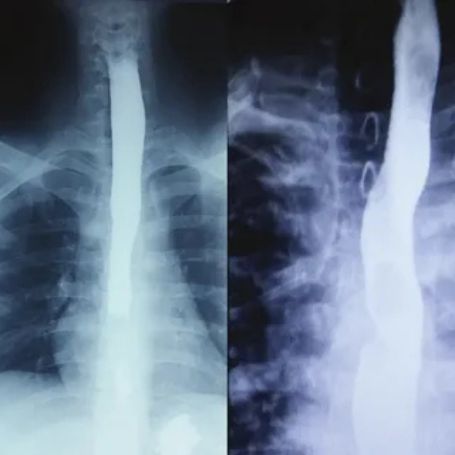

The Barium Meal Follow Through test is a specialized X-ray examination used to study the small intestine. This test helps doctors assess the movement and condition of the small bowel using a contrast agent called barium sulfate, which highlights the digestive tract clearly on X-ray images.

• Barium Consumption: You will drink a liquid containing barium sulfate. It coats the lining of your small intestine, making it visible under X-rays.

• X-ray Imaging: A series of timed X-rays are taken as the barium travels through your intestines. Images are captured at regular intervals until the barium passes into the large intestine.